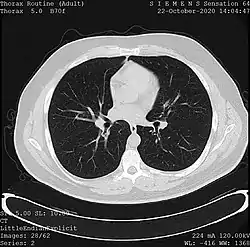

Tomography

- X-ray computed tomography (CT), or Computed Axial Tomography (CAT) scan, is a helical tomography technique (latest generation), which traditionally produces a 2D image of the structures in a thin section of the body. In CT, a beam of X-rays spins around an object being examined and is picked up by sensitive radiation detectors after having penetrated the object from multiple angles. A computer then analyses the information received from the scanner's detectors and constructs a detailed image of the object and its contents using the mathematical principles laid out in the Radon transform. It has a greater ionizing radiation dose burden than projection radiography; repeated scans must be limited to avoid health effects. CT is based on the same principles as X-Ray projections but in this case, the patient is enclosed in a surrounding ring of detectors assigned with 500–1000 scintillation detectors[13] (fourth-generation X-Ray CT scanner geometry). Previously in older generation scanners, the X-Ray beam was paired by a translating source and detector. Computed tomography has almost completely replaced focal plane tomography in X-ray tomography imaging.